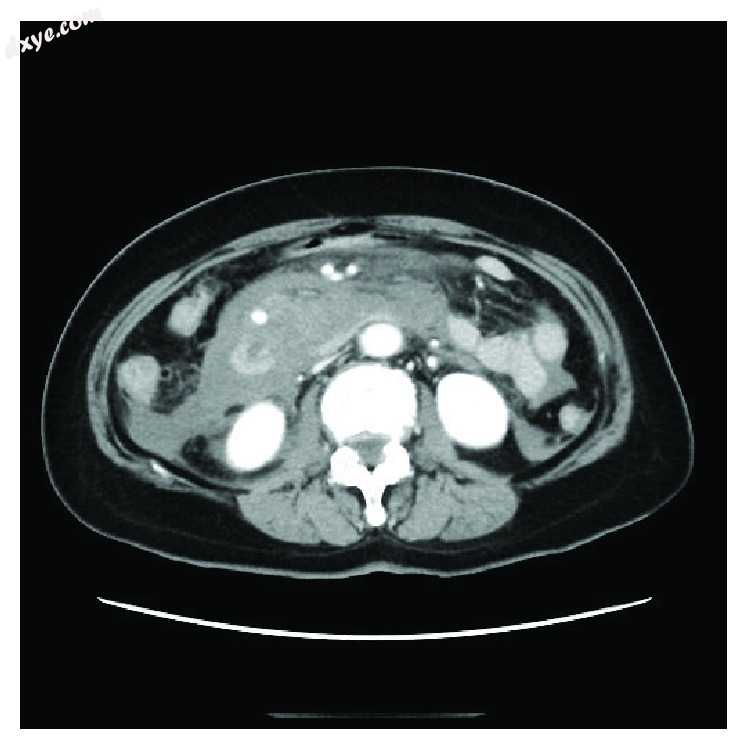

进行液体复苏后,患者的血压为129/94。实验室检查结果显示轻微的白细胞增多(15,600 /μl)和贫血(9.9g / dl)。 CT扫描显示大量腹水和动脉瘤(图1)。血管构造检查显示了胰十二指肠下动脉(IPDA)的动脉瘤和腹腔动脉根的狭窄(图2)。然后,作者进行了血管造影(图3),它也显示了IPDA的动脉瘤。作者尝试了线圈栓塞术,但是由于插入导管困难,作者中止了栓塞术,而是决定进行手术。作者以前没有MAL综合征的经验,鉴于紧急情况,作者选择了腹部手术。

1.jpg

图1

病例1:一名66岁的女性,CT扫描显示大量腹水和动脉瘤。